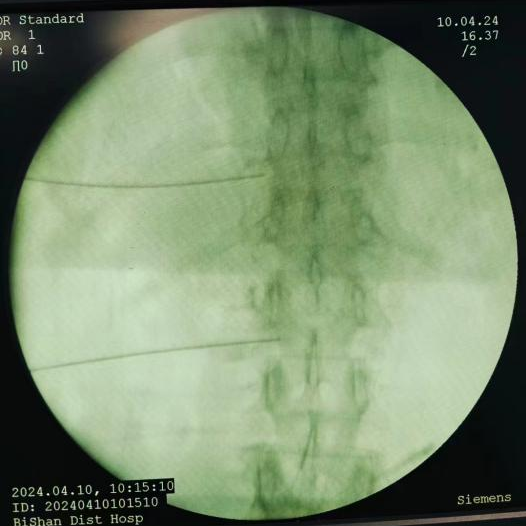

脊髓电刺激植入术:将电极植入脊柱附近硬膜外腔,通过电流刺激脊髓,阻断疼痛信号传至大脑,有效治疗慢性顽固性神经痛。

脊髓电刺激植入术